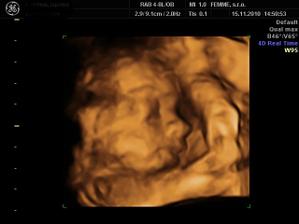

Nas druhy macko